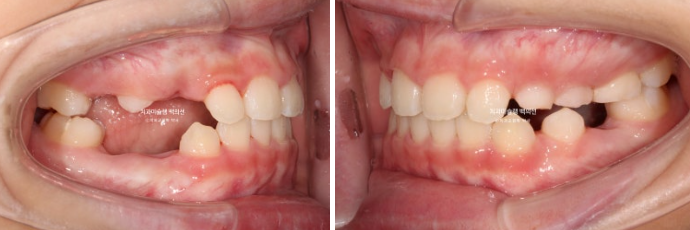

2022년 8월 내원한 어린이 입니다.

앞니 반대교합과 비대칭 치료를 위해 오셨습니다.

앞니 뿐 아니라 송곳니, 일부 어금니까지 거꾸로 물리는 상황입니다.

앞니 반대교합은 프리올소와 같은 장치로 간단하게 넘겨줄 수 있지만 더 큰 문제는 비대칭입니다.

아래앞니와 함께 아래턱이 우측으로 돌아가 있습니다.

골격분석 결과 페이스마스크와 같이 적극적인 주걱턱 치료는 불필요하고 가성주걱턱일 가능성이 높아 간단하게 반대교합 부터 넘기기로 합니다.